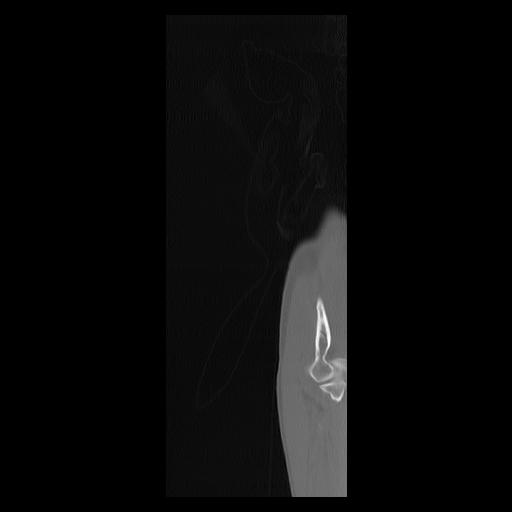

33 PULMON,CE,Sagittal,3.000,PULMON,Sagittal,